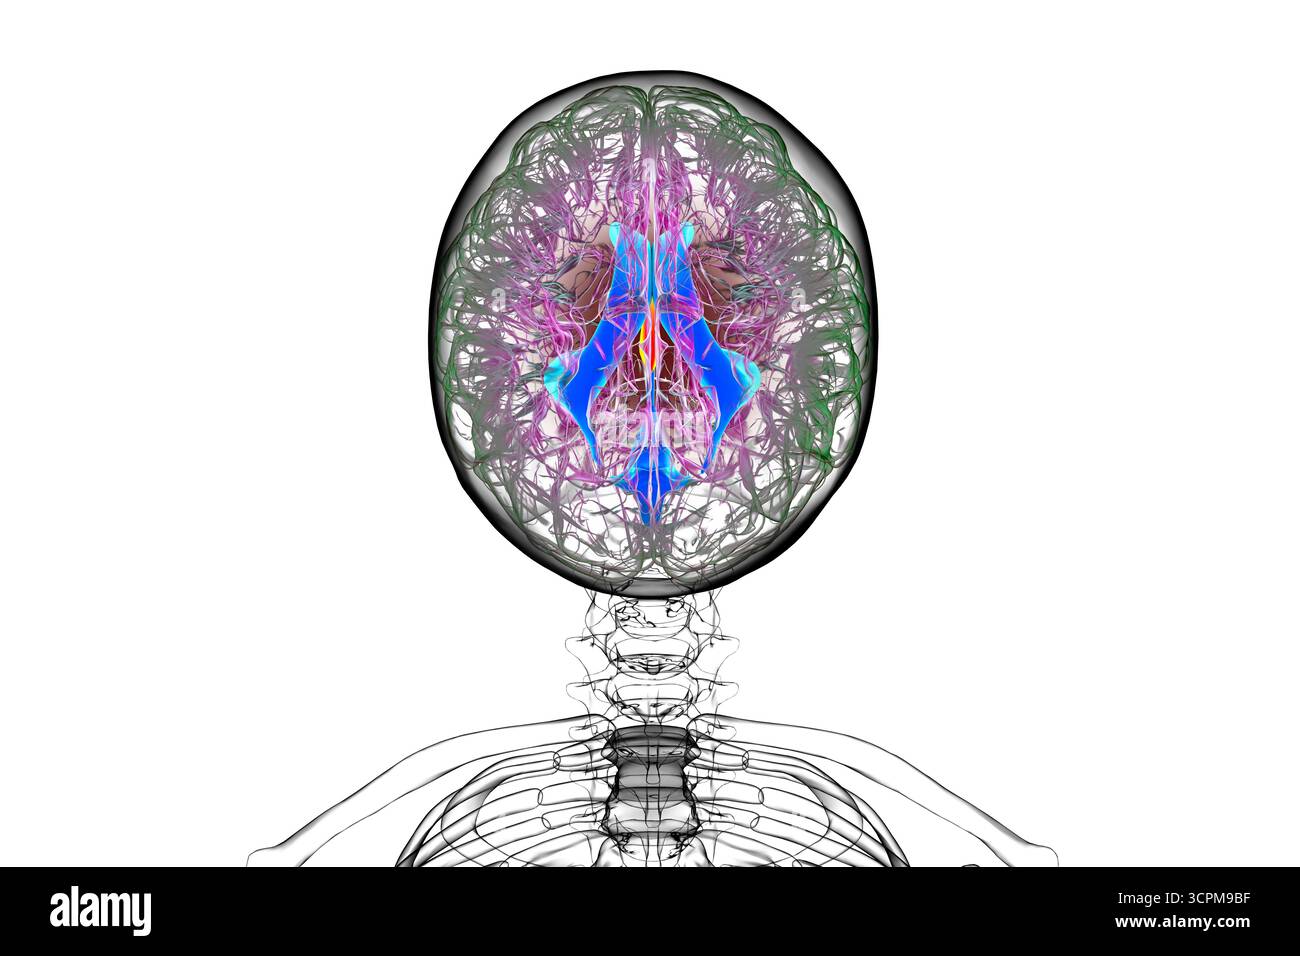

RF3CN8WHP–Illustration des vergrößerten lateralen und dritten Ventrikels des Gehirns (Hydrozephalus), hervorgerufen durch einen Hirntumor, der den Aquädukt des Gehirns komprimiert.

RF3CPM9C1–Illustration des dritten Hirnventrikels, einer lebenswichtigen Komponente des Hirnventrikulärsystems.

RF3CPM9BH–Illustration des dritten Hirnventrikels, einer lebenswichtigen Komponente des Hirnventrikulärsystems.

RF3CPM9BF–Illustration des dritten Hirnventrikels, einer lebenswichtigen Komponente des Hirnventrikulärsystems.

RF3CPM9BE–Illustration des dritten Hirnventrikels, einer lebenswichtigen Komponente des Hirnventrikulärsystems.

RF3CPM9BX–Illustration des dritten Hirnventrikels, einer lebenswichtigen Komponente des Hirnventrikulärsystems.